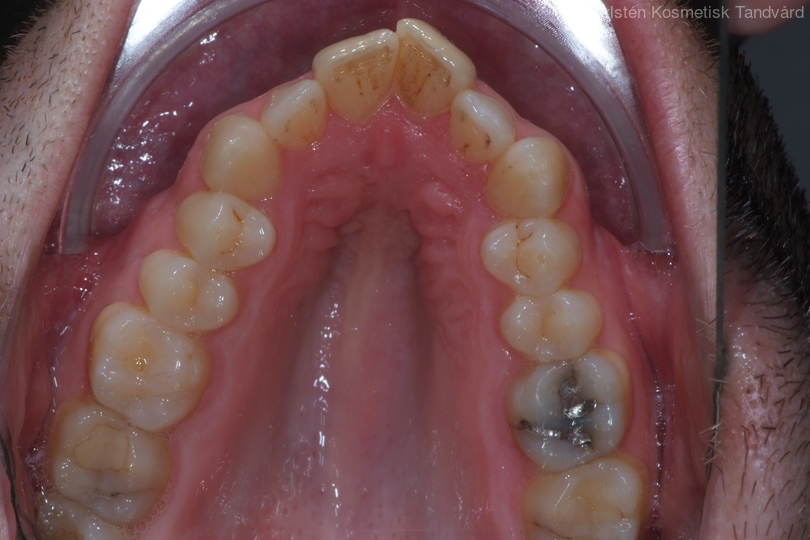

Tandreglering 3

35-årig man med smal och trångställd tandbåge. Vill ha ett jämnt leende. Behandling bestod av knappt 9 månader med genomskinliga Invisalignskenor.